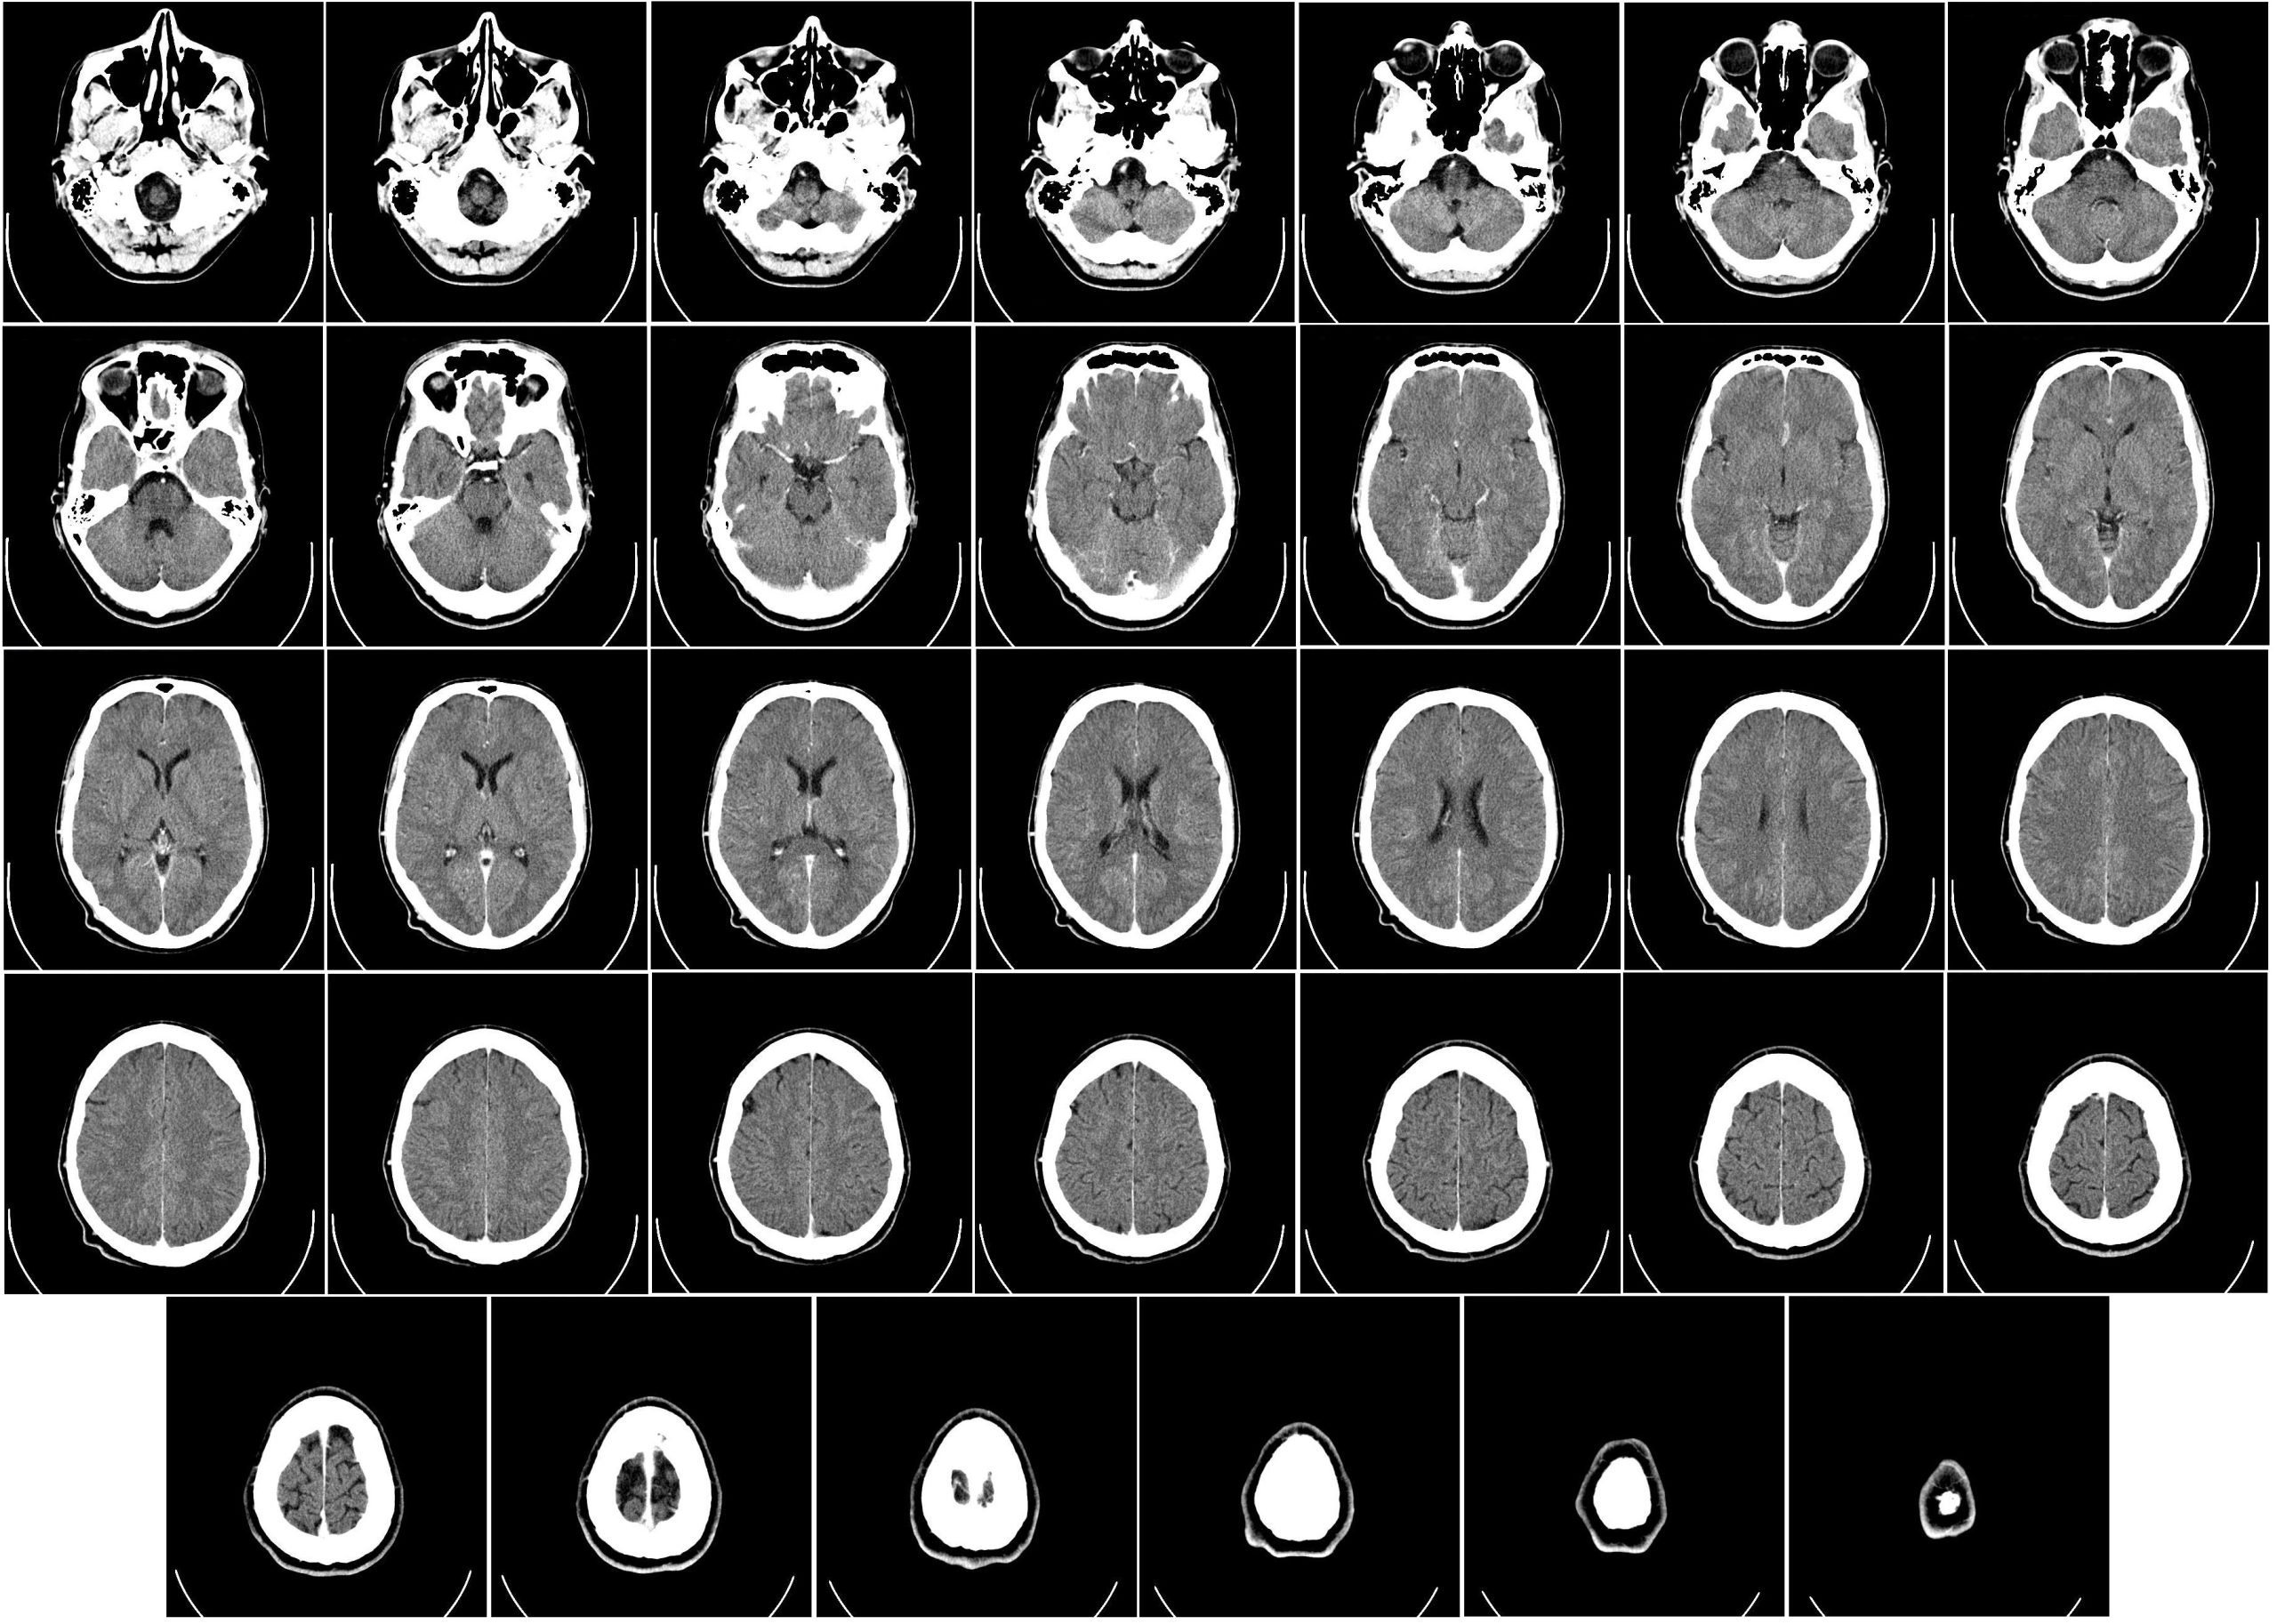

Diagnostic radiography focuses on using scanning machines in order to detect and diagnose sickness or injuries inside the body.

Medical imaging technology is a branch of radiography that is focused on the maintenance, management, and operation of imaging equipment and machines that are used for scanning.